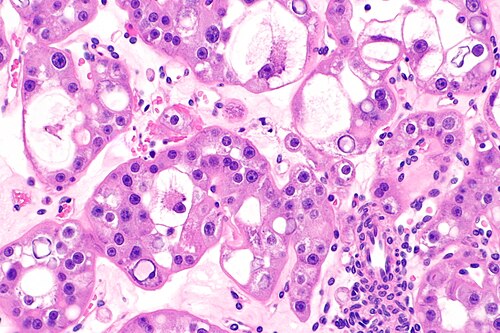

1

Diagnosis?

Clear cell renal cell carcinoma -- intermed mag.jpg